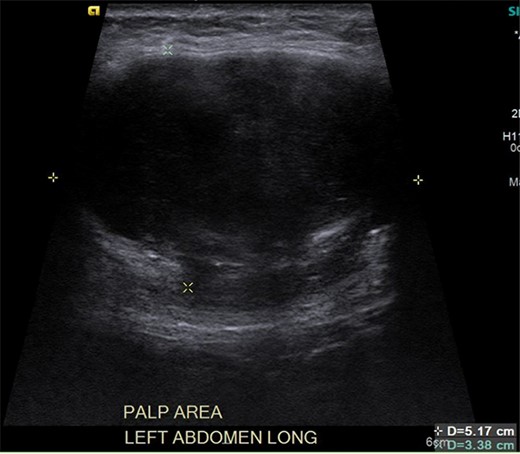

Ultrasound reveals an enlarged solid mass with internal vascularity.

It was difficult to delineate whether the mass was primarily cystic or solid based on the initial CT, so an ultrasound was ordered. The ultrasound revealed the mass had enlarged, now measuring 5.7 × 3.6 × 4.7 cm. Internal vascularity was present, making the diagnosis of a solid mass more likely than a seroma (Fig. 2). An MRI redemonstrated the mass embedded in the left rectus muscle (Fig. 3). It had well-defined margins with high signal intensity on T2 sequence and low signal intensity on T1. On post-contrast sequences, the mass had homogeneous enhancements and a thick enhancing wall, most compatible with an intramuscular myxoma. However, without tissue biopsy, other solid tumors could not be dismissed, such as desmoid.